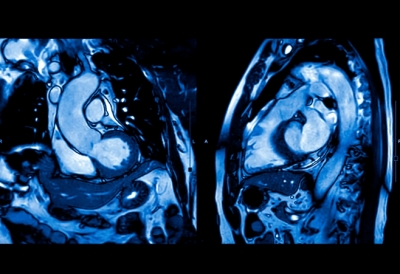

Σε αυτές τις περιπτώσεις, ο γιατρός προτείνει τη χρήση καρδιακής μαγνητικής τομογραφίας υπό κόπωση (stress cardiac MRI), η οποία επιτρέπει την παρακολούθηση της ροής του αίματος στην καρδιά ενώ ο ασθενής βρίσκεται σε κατάσταση «άσκησης». Αυτή η μέθοδος, σύμφωνα με τον Berry, είναι ιδιαίτερα χρήσιμη στις γυναίκες, που συχνότερα παρουσιάζουν στηθάγχη μικρών αγγείων, η οποία συχνά περνά απαρατήρητη.

Η ερευνητική ομάδα μελέτησε 250 ενήλικες με πόνο στο στήθος αλλά χωρίς φραγμένες αρτηρίες σύμφωνα με την αγγειογραφία. Όλοι υποβλήθηκαν σε εξέταση stress MRI καρδιάς, με στόχο να εντοπιστούν πιθανά προβλήματα στη ροή αίματος των μικρότερων αγγείων.